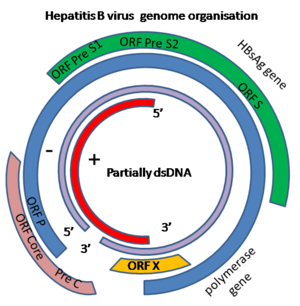

الجينوم

جينوم ڤيروس الالتهاب الكبدى ب عبارة عن الحمض النووي الدائرى، ولكن ليس من المعتاد لان الحمض النووي ليس مزدوج الشرائط تماماً. وترتبط احدى نهايات الشرائط الكاملة من بوليميريز الحمض النووي الڤيروسي. والجينوم هو 3020-3320 طول النيوكليوتيدات (بطول الشريط الكامل) و1700-2800 طول النيوكليوتيدات (للشريط القصير الطول).[12] ويعتبر بمعنى سلبي، (غير مرمز)، مكملا للحمض النووى الڤيروسي RNA. ويوجد الحمض النووي الڤيروسي في أقرب وقت بعد إصابة نواة الخلية. يذيب الحمض النووي المزدوج جزئيا إلى مزدوج كاملا بالانتهاء من (+)الجزئ الحساس، وحذف جزيء من البروتين (--) الجزئ الحساس وسلسلة قصيرة من الحمض النووى RNA من سلسلة نشيطة(+). ويتم إزالة قواعد غير الترميز من طرفي (--) الشريط الحساس وترتبط النهايات. هناك أربعة جينات مشفرة بالجينوم تدعى C,X,P,S. ويوضح الترميز للبروتين الأساسي بالجين C (HBcAg)، ويسبق بدء تسلسل معلومات النظام الجيني بالتنقيب والإنتاج في إطار أغسطس بدء تسلسل معلومات النظام الجيني من إنتاج البروتين المنتج للأساسي. ينتج HBeAg من عملية تحلل البروتينات للبروتين قبل الاساسى. ويُشفر بوليميريز الحمض النووى بواسطة جينP. جين S هو الجين الذي يرمز لمضاد الجين السطحي (HBsAg). الجين HBsAg هي اطار واحد طويل مفتوح للقراءة ولكن الإطار يحتوي على ثلاثة في إطار "بداية" الرمز الجينى الذي يقسم الجينات إلى ثلاثة أقسام، قبل S2، قبل S1، S ونظرا لبدء الكودن المتعدد، ثلاثة أنواع من البروتينات المتعددة مختلفة الأحجام تدعى الكبيرة والمتوسطة والصغيرة (ما قبل S1+ قبل S2+ S، قبل S2+ S أو S) يتم إنتاجها.[13] يُرمز وظيفة البروتين للجين X ليست مفهومة تماما.[14]